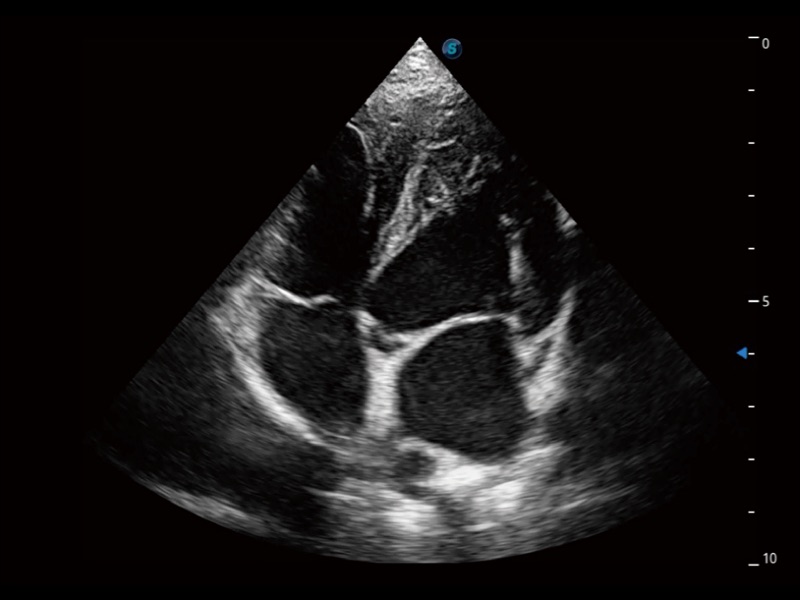

• Auto EF 心内膜自动描迹

能够基于左心室壁追踪和辛普森法,自动计算射血分数,支持多个可移动点描迹,与手动测量相比,极大节省了动物医生的时间和精力。

• AMM 解剖M型

通过360度任意调节3条M型取样线,在同一心动周期上观察心脏不同位置的运动曲线,得到准确的心功能测量数据,有效评估心肌运动及左心室功能。

• TDI 组织多普勒成像

实时用颜色表示心肌组织运动,观察和定量组织的运动情况,对快速检测与评估心肌的灌注和活性、电传导及心肌收缩和舒张功能等均能提供重要的诊断信息。

优异的基础图像

ProPet 70 全新的动物超声智能软件和丰富的探头群,为动物医生提供了高清晰度和精细分辨率的图像,无论在宠物、马科、畜牧还是实验室动物等应用中都可以轻松应对,为您的日常工作带来满意的体验。

(犬)四腔心

(犬)四腔心MQA